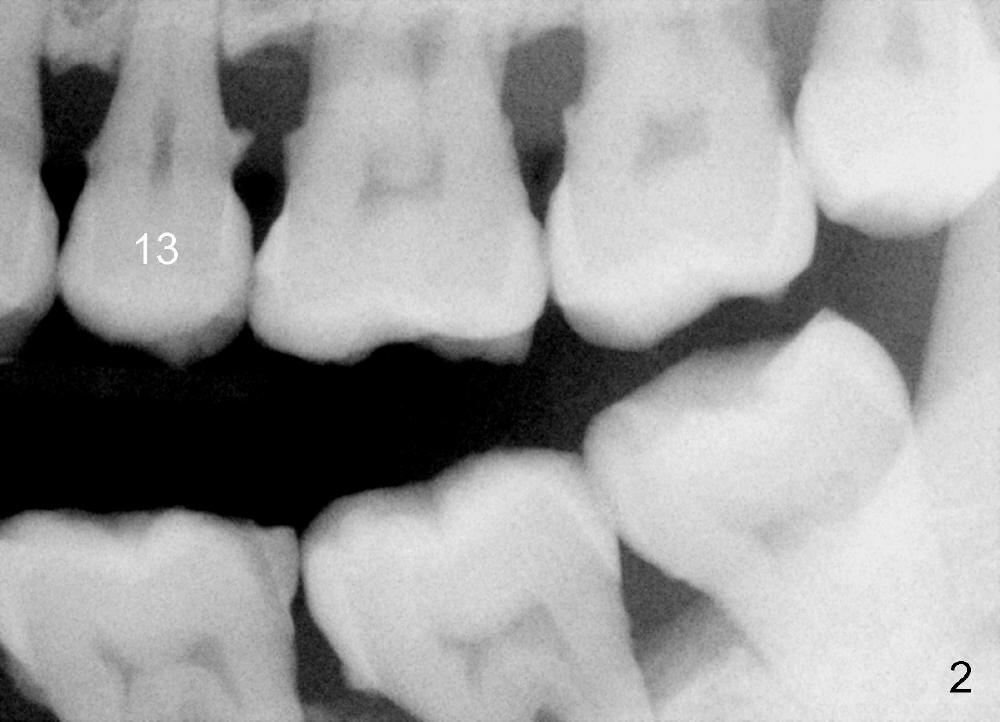

A 57-year-old man has history of chronic periodontitis (Fig.1,2, taken 9 and 7 years ago, respectively). Last April the tooth #13 had crown fracture (Fig.3). He returned to clinic for scaling & root planing last week (Fig.4). Fig.3,4 show long root and bone. Arrowheads in Fig.4 indicate the sinus floor.